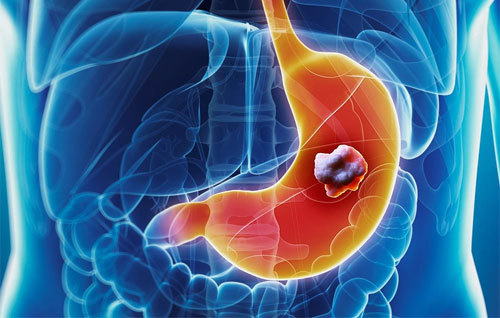

위암은 위에 생기는 악성 종양으로, 일반적으로 위의 내벽에서 시작됩니다. 위암의 원인은 다양하지만, 헬리코박터 파일로리 감염, 식습관, 유전적 요인 등 여러 가지가 복합적으로 작용할 수 있습니다. 위에서 발생한 암이 주변 장기로 전이될 수 있으며, 이로 인해 치료가 복잡해질 수 있습니다.